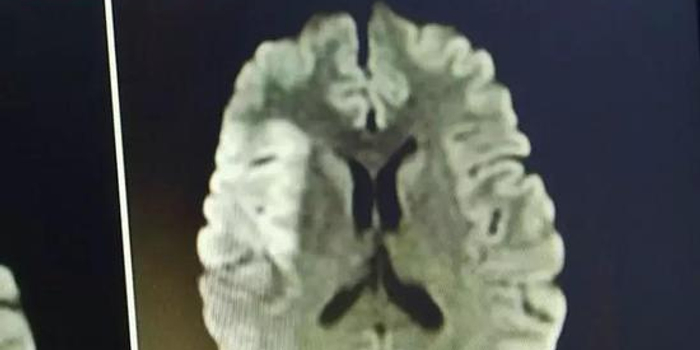

当时阿兰的脑部状况已经十分严重

医生为她取出了2公分的血栓

这是一般患者的2倍!